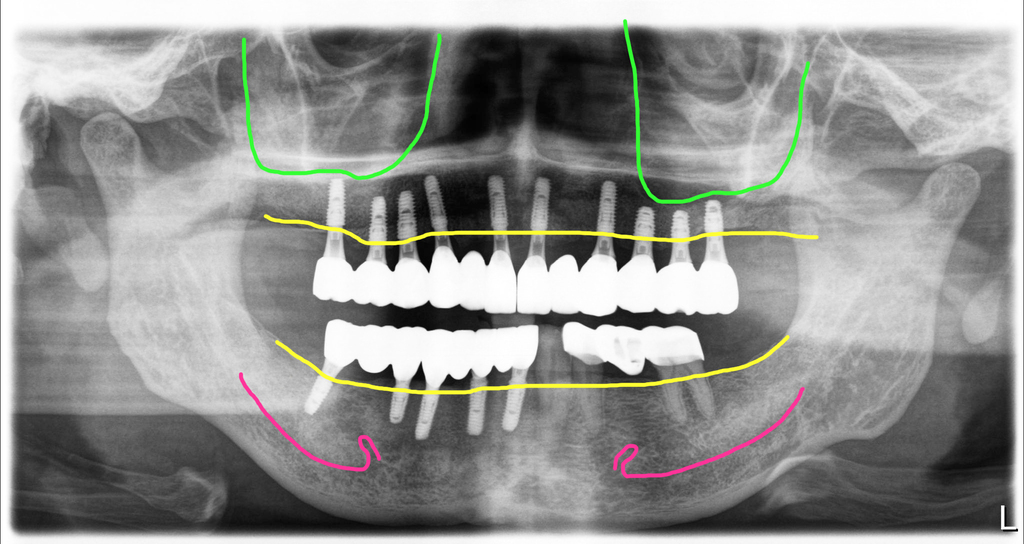

왼쪽 위에 치아가 여러개 없지만 오른쪽으로 계속 드시면서 치료를 미루고 계셨던 분입니다. 치아상태가 좋지 않다는 것은 알았지만 치아뿌리 속의 상태나 뼈의 상태는 환자는 알 수가 없잖아요. 오른쪽 마져 이제 씹는 것이 힘들어져서 전체적으로 치료를 하러 오셔서 파노라마 엑스레이를 찍었습니다.

위쪽에 남아있는 치아들도 치조골이 거의 녹아서 장기간 버틸 수 없는 상태였고, 아래쪽은 오른쪽에는 작은어금니 부위에 염증이 너무 심하게 진행되어 턱뼈가 아주 심하게 파괴되어 있었습니다.

이렇게 빨강색 선인 신경까지 염증(노랑색선)이 진행되어 해당 부위에는 임플란트를 식립할 수가 없는 상태였습니다. 억지로 심게 되면 신경손상 가능성이 아주 높아집니다.